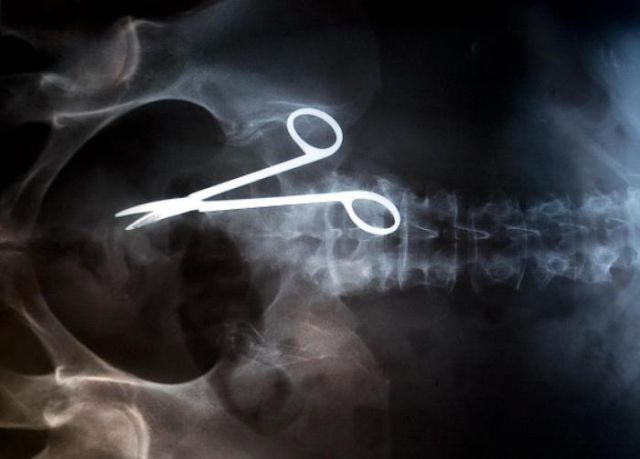

These x-rays will make you wonder how this could ever have happened in the first place.

The items are not bizarre at all... car keys, nails, a fork, scissors... nope.. nothing bizarre so far... a goblin on a tiny dragon would've been bizarre indeed..